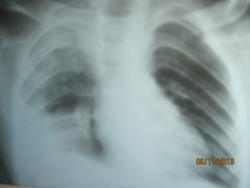

Cредостение на месте. Написала инфильтрация S1, 2, 3, 5 Пневмония без динамики. Завтра снова хотят контроль делать и рентгена и УЗИ.

аспирация не исключена